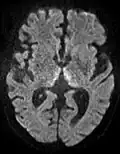

DWI showing restricted diffusion in the medial dorsal thalami consistent with Wernicke encephalopathy

DWI showing restricted diffusion in the medial dorsal thalami consistent with Wernicke encephalopathy -